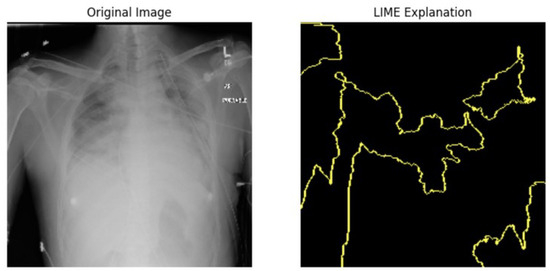

5.4.1. Local Interpretable Model-Agnostic Explanations for Clinical Validation

We applied scientific analysis on a random 7 sample, which was provided by the clinical specialist. The LIME Analysis for Image Data (a), (b), (c), (d), (e), and (f) is in Figure 22, Figure 23, Figure 24, Figure 25, Figure 26 and Figure 27. There are two parts of LIME analysis from the provided chest X-ray images to detect the disease area. Original Image and LIME explanation;

• Original Image: The patient’s thoracic cavity. It displays the typical anatomical structures of the chest, including the lungs, ribs, and heart.

• LIME Explanation: The result of applying LIME to the chest X-ray image. The yellow boundaries indicate the regions of the image that were most influential in the model’s decision-making process when determining whether the image indicated a particular condition. In this context, these regions are the parts of the X-ray that the AI model considered most important for making its diagnostic prediction.

The analysis very useful for clinicians to understand the model’s behavior and ensure that it aligns with medical expertise. The use of LIME helps in making the AI model’s interpretability decisions more transparent and interpretable. It allows medical professionals to verify whether the AI’s focus areas correspond to clinically significant regions. It also enhanced diagnostic capability of understanding which parts of the images in the AI model in refining the model further and ensures that it makes accurate and reliable predictions. This is particularly crucial in medical diagnostics where interpretability and accuracy are paramount.

Figure 24. LIME Analysis for Image Data (c) on original image to LIME explanation.